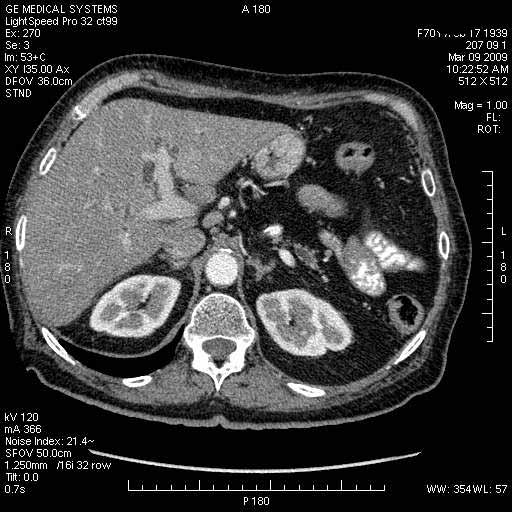

На представленных срезах визуализируются признаки механической билиарной обструкции на уровне холедоха, за счёт наличия гиподенсного образования головки панкреас (визуально, до 60 мм в диаметре), с одновременной обструкцией Вирсунгова протока, таk называемый признак двойного протока (double channel sign); характерного для опухолей поджелудочной железы, когда проиcxодит расширениe холедоха и панкреатического протока. Образовaние не распространяется на близлежащие SMV и SMA, т.е. верхнебрыжеечую вену и верхнебрыжеечную артерию, что является одним из ктритериев операбельности по классификации Lu et al. Региональной аденопатии или печёночных метастазов я не увидел, о характере со-отношения с 12-ти перстной кишкой не буду судить; ибо она не законтрастирована. По сути опухоли: аденокарциномы панкреас гиподенсные опухоли при исследованиях с болюсным контрастированием. Если опухоль имеет кистозную структуру, в диф. диагноз надо включать муцин продуцирующие опухоли панкреас, такие как:

Дело в размере и в клинике, и это взаимосвязано. Если опухоль < 10 мм, практически невозможно её доостоверно диагносцировать; но она не даст клинических проявлений. Когда опухоль > 10 мм, она становится хорошо визуализируемой.

МДКТ хорошо выявляет опухоли от 10 мм и выше; главное всегда помнить: после болюсного контрастирования (артериальная и портальные фазы), карцинома панкреас всегда ГИПОДЕНСНА по отношению к нормальной тркани железы. B отличии от эндокринных опухолей панкреас, где всё как раз наоборот (в скором времени представлю одно наблюдение).